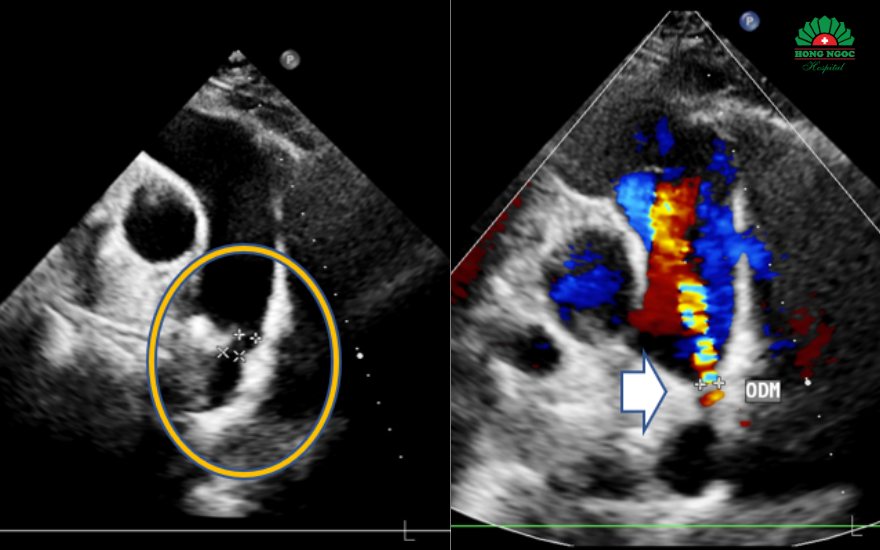

Hình ảnh siêu âm ghi nhận còn ống động mạch

Chưa đầy một giờ đồng hồ, ê kíp đã thành công bít hoàn toàn ống động mạch cho bệnh nhân. Hình ảnh siêu âm sau can thiệp cho thấy không còn dòng chảy bất thường, dụng cụ cố định vững chắc. Chị N. nhanh chóng cải thiện triệu chứng, ổn định và xuất viện chỉ sau 2 ngày.